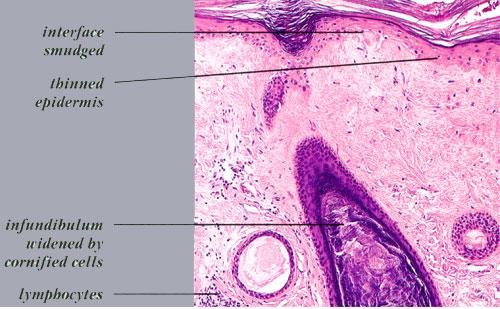

Alopecia of Discoid Lupus Erythematosus = الحاصة بسبب الذئبة الحمامية القرصية